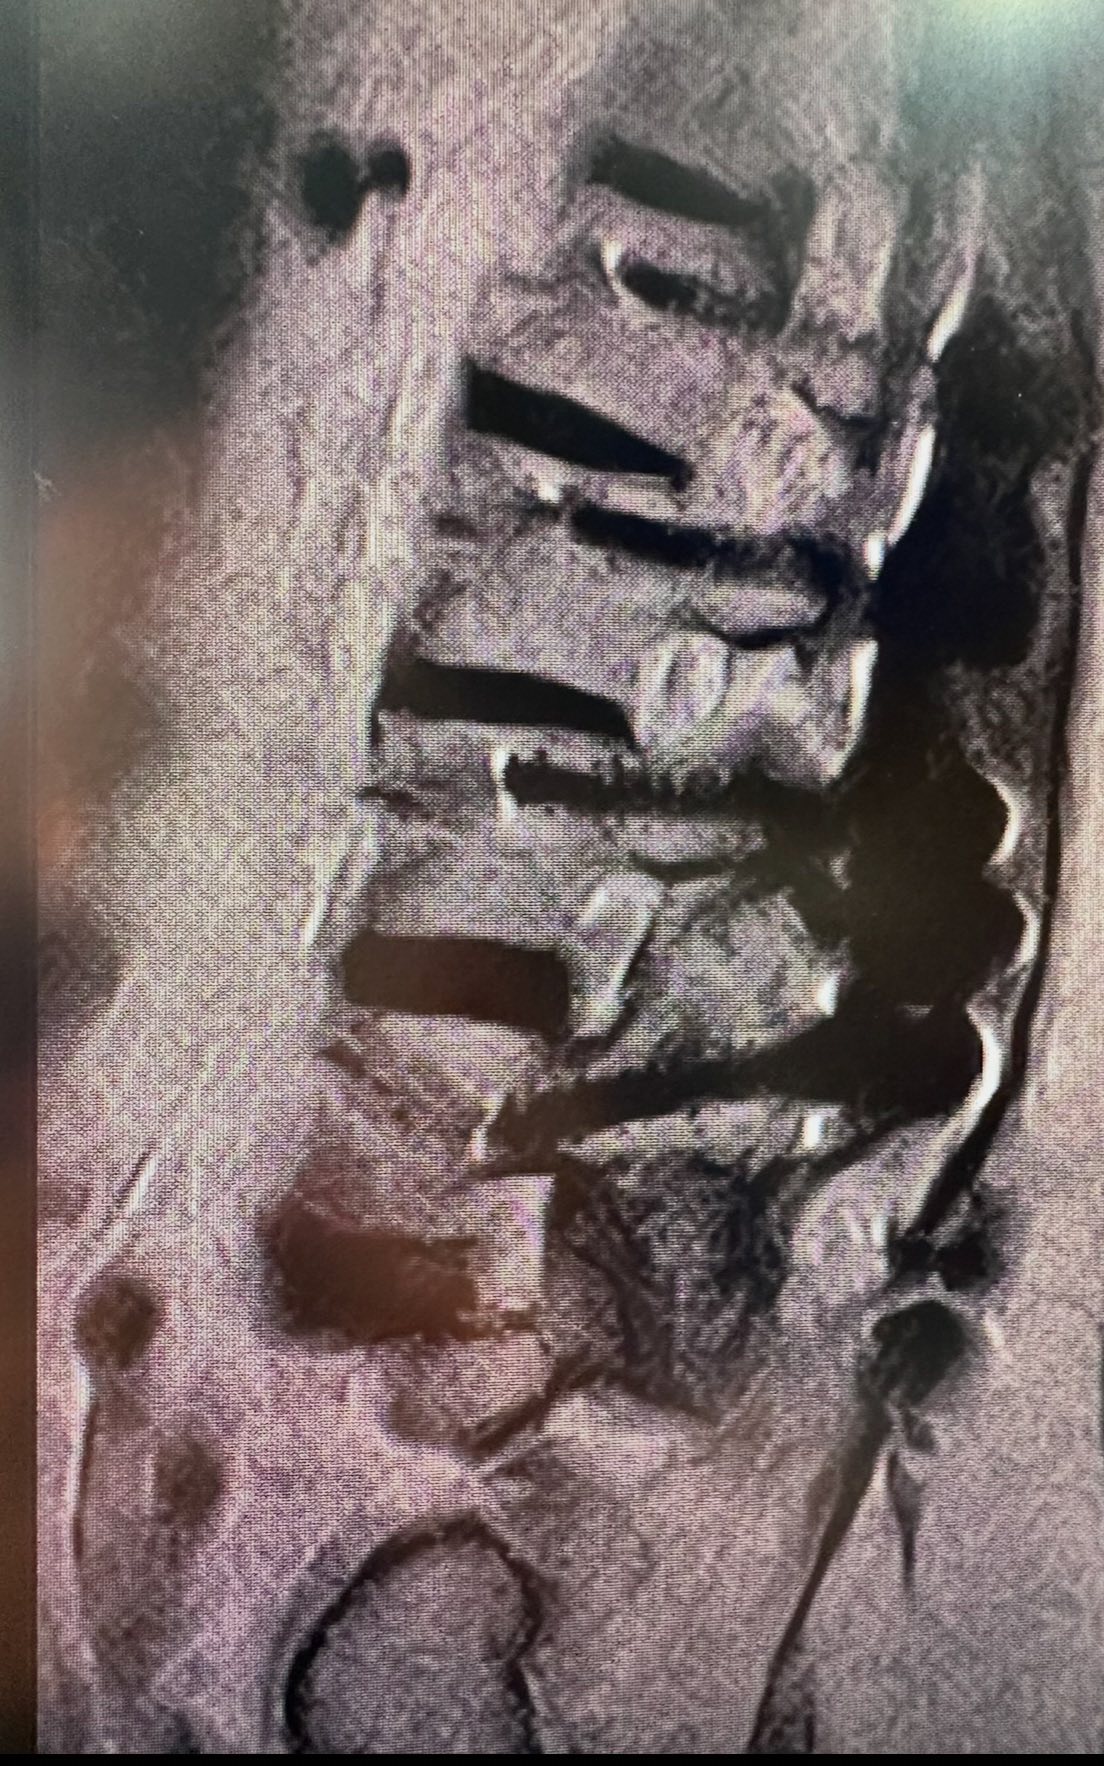

MRI 影像:在術後的區域,可以清楚看見沾黏與纖維化,像荊棘般纏繞在神經周圍,讓原本應該獲得解脫的身體,再度陷入酸、麻、痛的深淵。